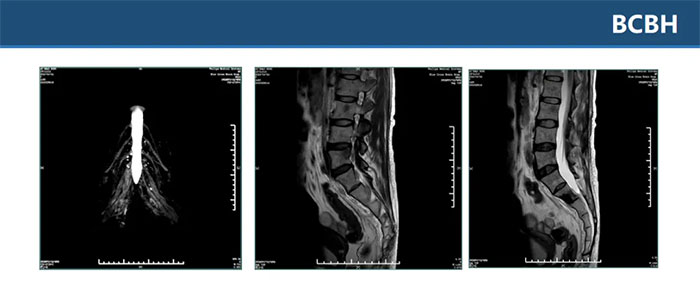

▲ 双侧骶丛神经平扫+增强未见明显异常,L2、L4、骶S1-3椎体及其附件区多发异常信号影

▲ 双侧坐骨、髂骨、骶骨、左侧耻骨多发异常信号伴左髂骨髋臼处骨质破坏,考虑肿瘤性病变,转移瘤待排